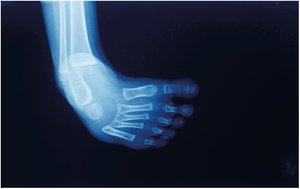

Ankle and Foot

Tarsals: Seven ankle bones

Metatarsals: Five midfoot bones

Phalanges: Toe bones (three per toe, two in hallux/great toe)